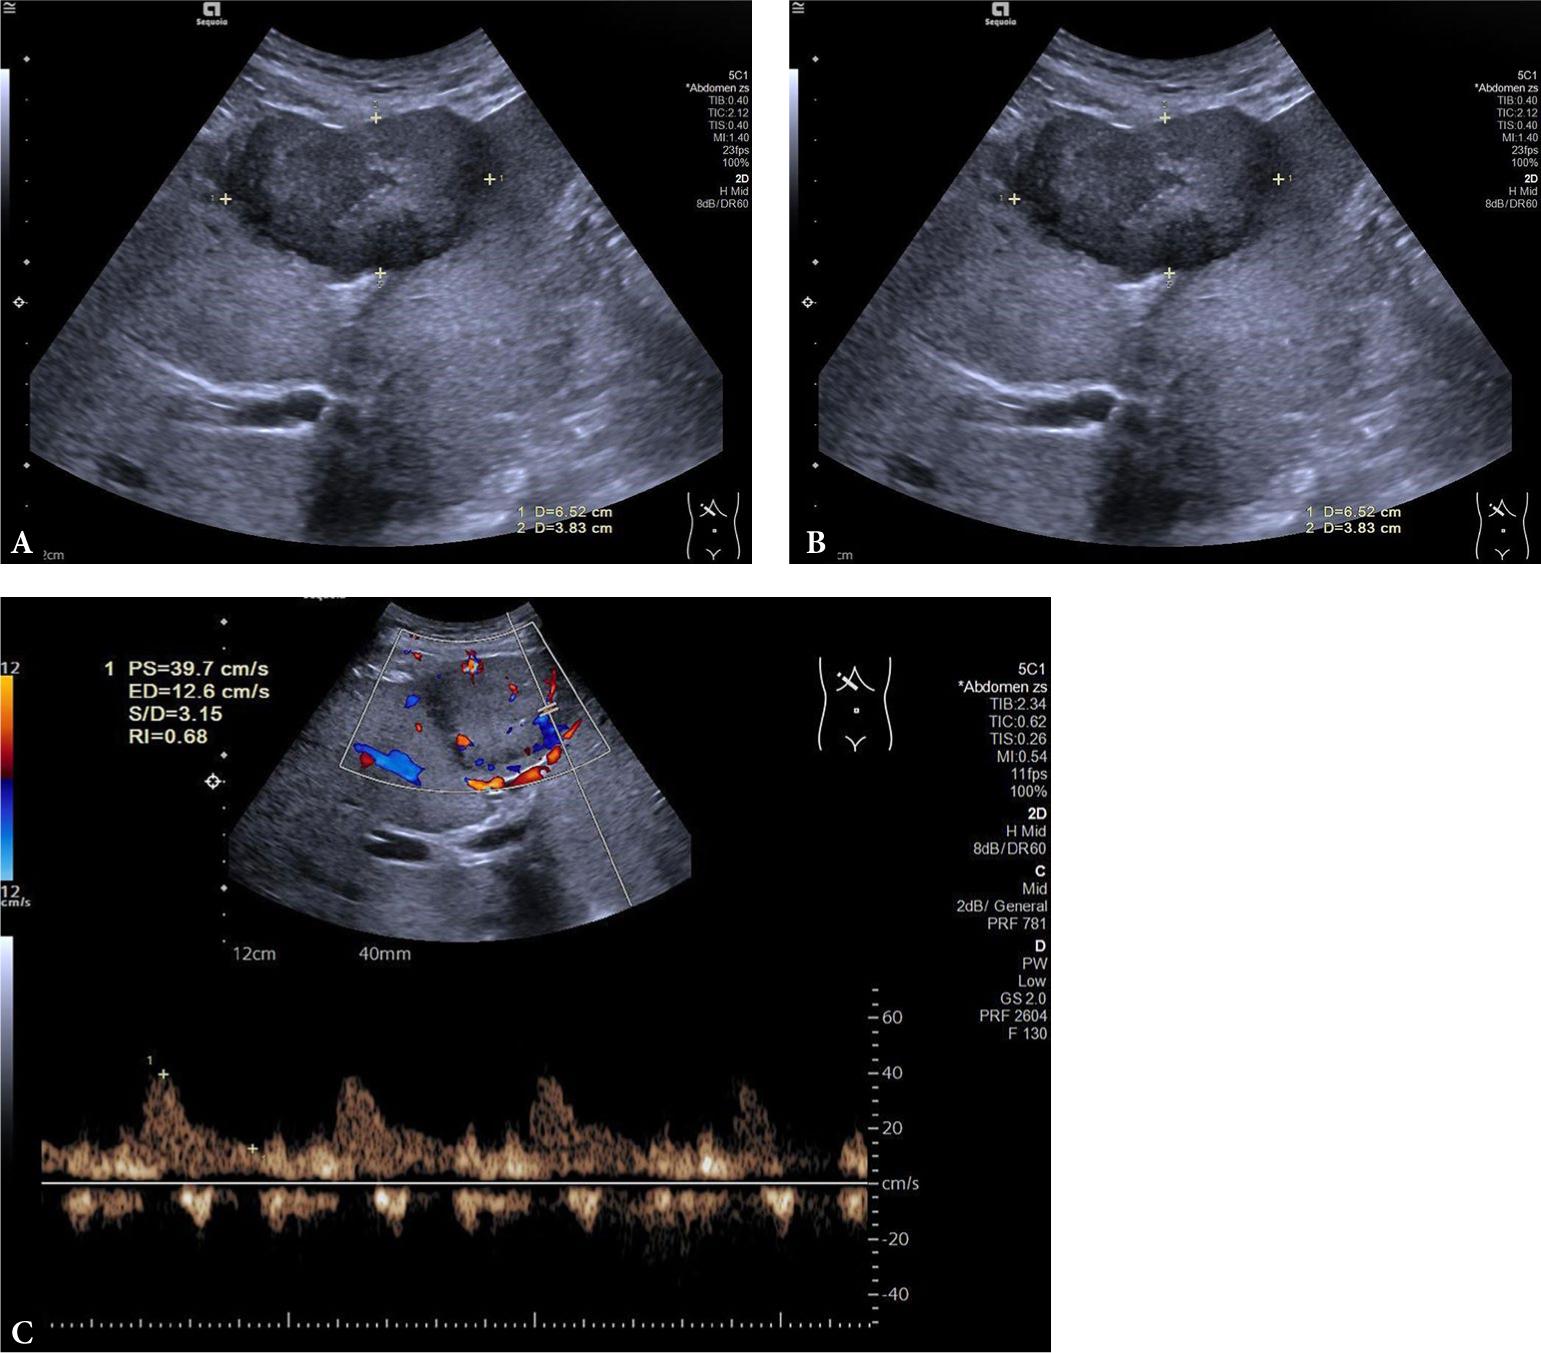

Fig. 1.